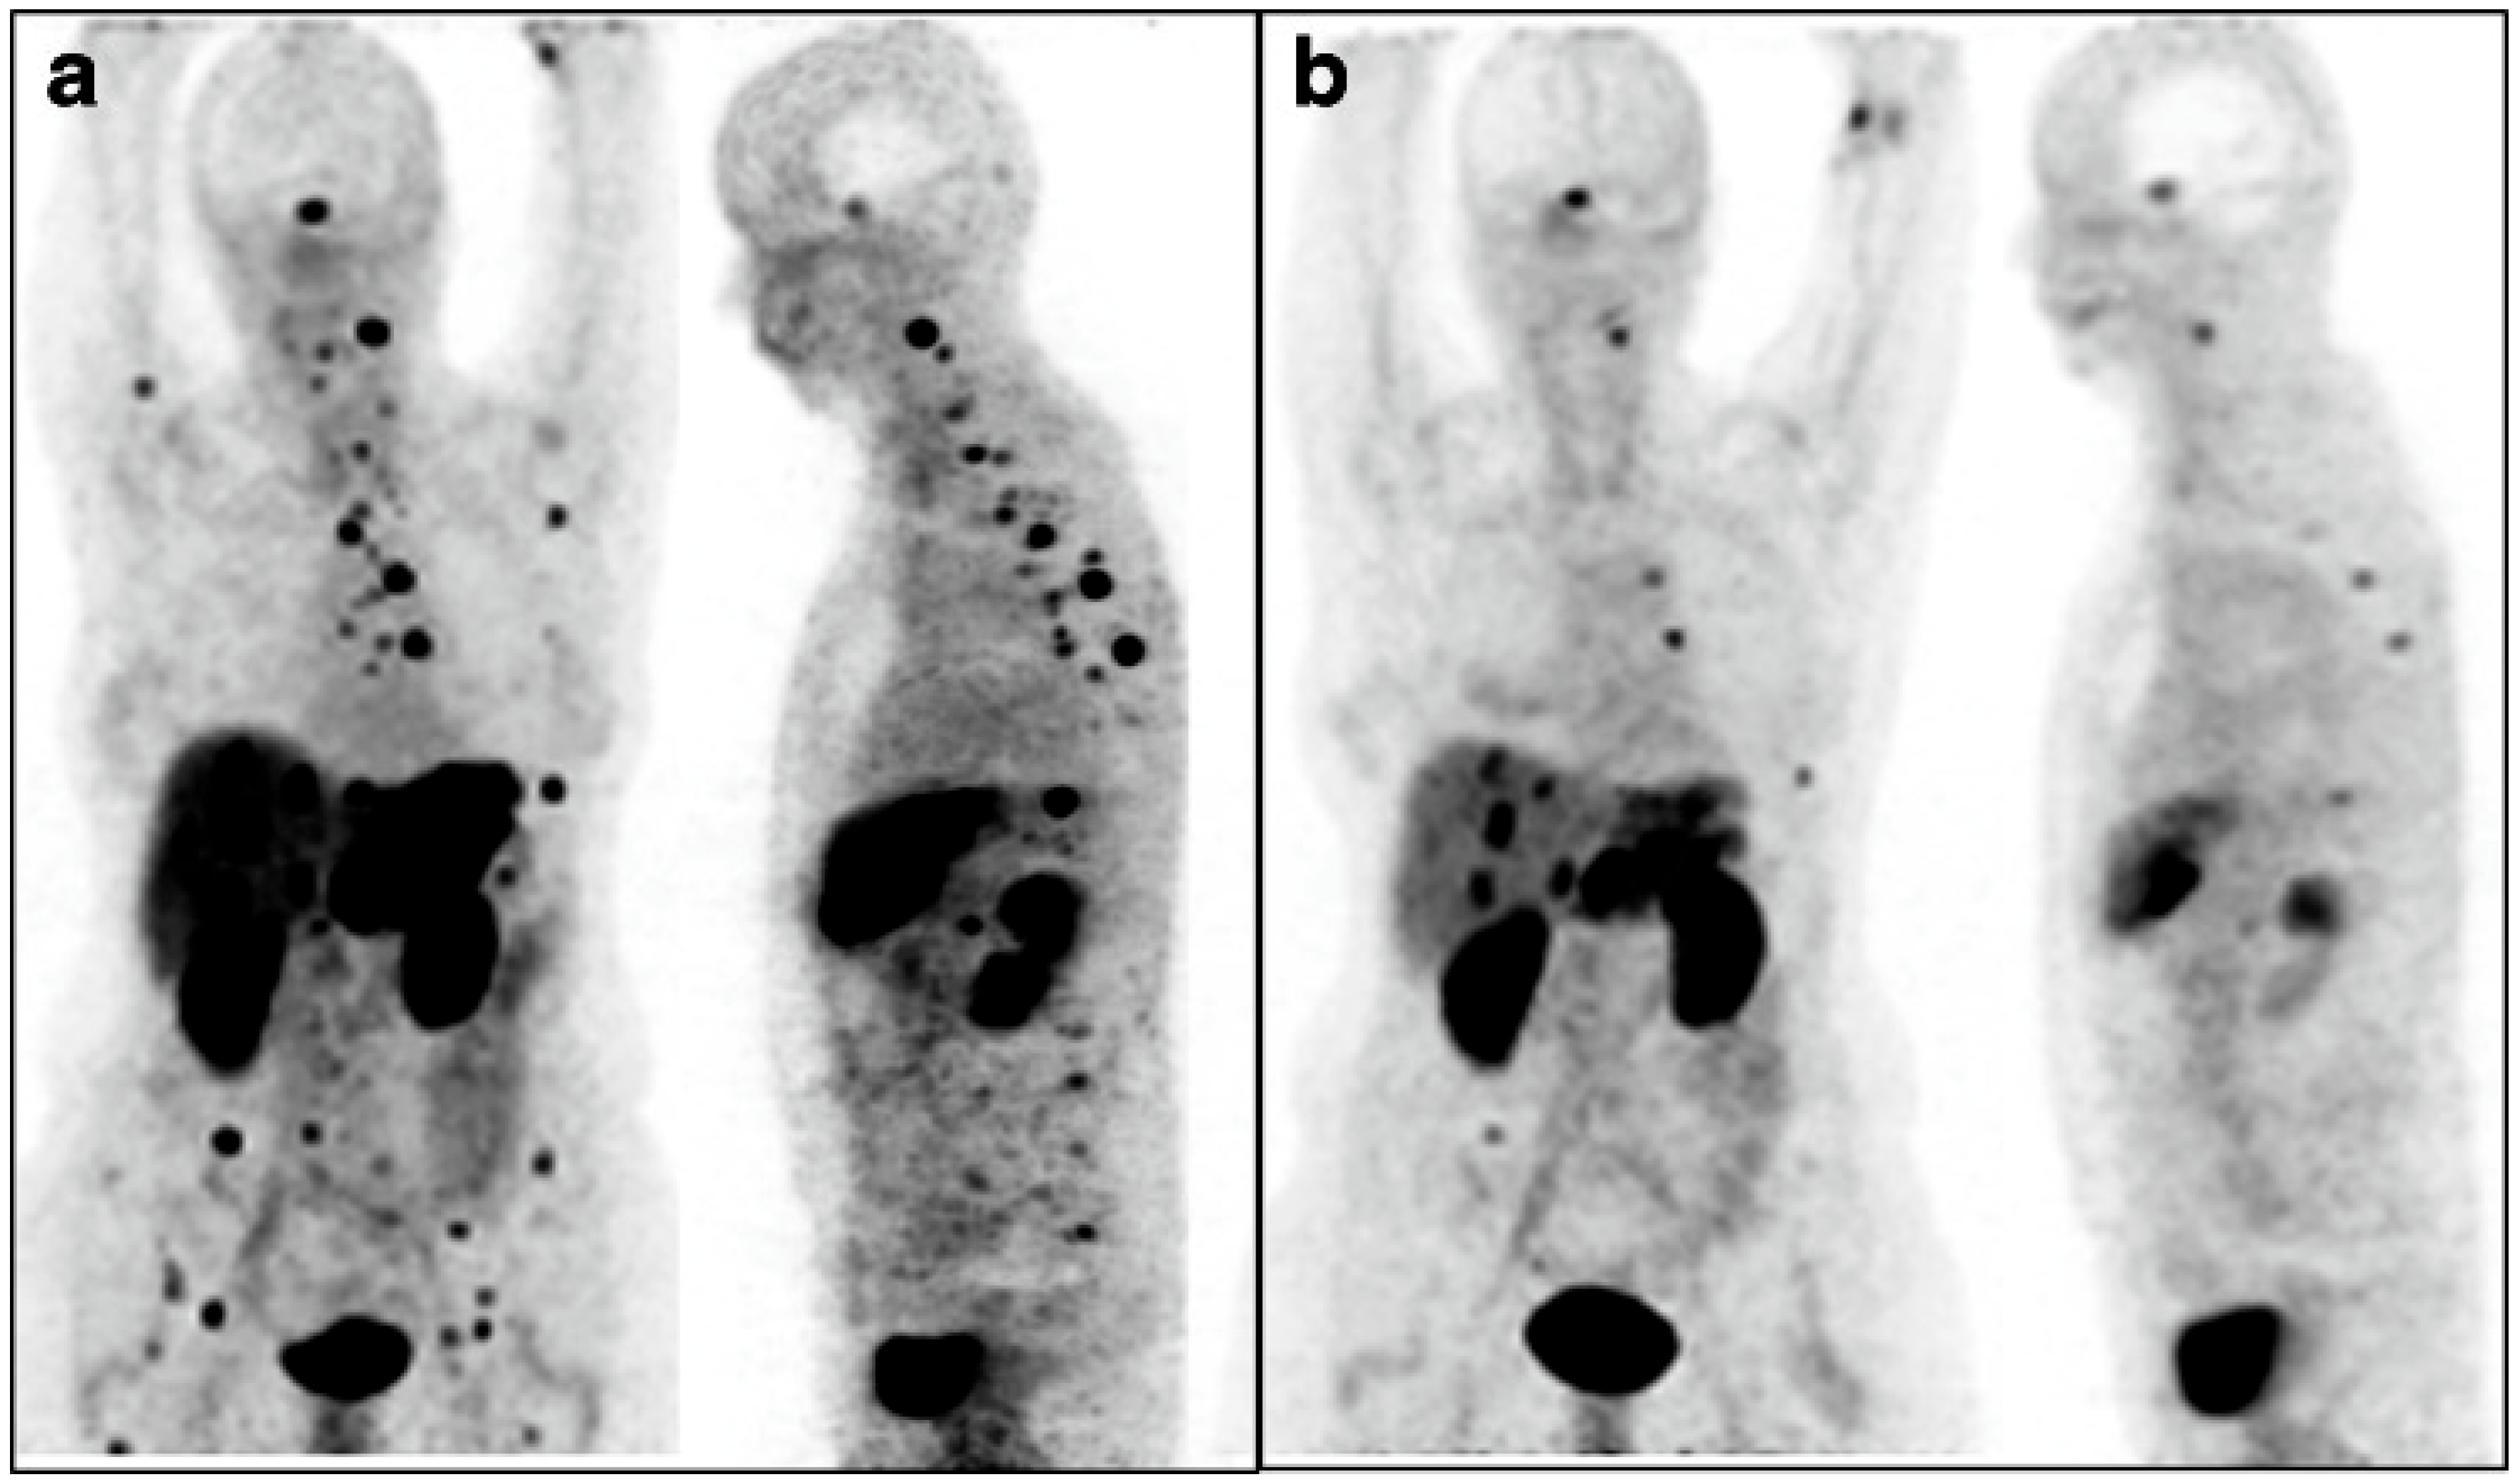

- Ballal, S.; Yadav, M.P.; Bal, C.; Sahoo, R.K.; Tripathi, M. Broadening horizons with 225Ac-DOTATATE targeted alpha therapy for gastroenteropancreatic neuroendocrine tumour patients stable or refractory to 177Lu-DOTATATE PRRT: First clinical experience on the efficacy and safety. Eur. J. Nucl. Med. Mol. Imaging 2020, 47, 934–946. [Google Scholar] [CrossRef]

- Ballal, S.; Yadav, M.P.; Tripathi, M.; Sahoo, R.K.; Bal, C. Survival Outcomes in Metastatic Gastroenteropancreatic Neuroendocrine Tumor Patients receiving Concomitant 225Ac-DOTATATE Targeted Alpha Therapy and Capecitabine: A Real-world Scenario Management Based Long-term Outcome Study. J. Nucl. Med. 2023, 64, 211–218. [Google Scholar] [CrossRef]